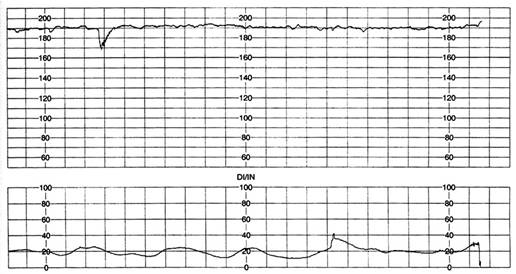

Fig. nr.292 RCFB normal

Inainte de 32 saptamani, de obicei fetii sunt cu RCFB usor mai crescut, apoi RCFB este intre 120 - 160 bpm,( se accepta si 110 - 150 bpm ) ca dupa 42 saptamani sa scada la 100 - 110 bpm.

Variabilitatea RCF este data de influenta simpaticului si a parasimpaticului.

Cel mai usor de demonstrat, este incadrarea RCFB intre doua benzi orizontale, la limita inferioara si superioara a traseului, cu masurarea distantei intre aceste doua linii. Variabilitatea normala este intre 5 si 15 bpm in timpul sarcinii , creste la 5 - 25 bpm in travaliu. Variabilitatea apare dupa 26 - 28 saptamani , odata cu maturarea centrilor nervosi si creste cu varsta gestationala.

Fig . nr. 293 Exemplu de masurare a variabilitatii RCF , intre doua linii,trecerea din starea de somn linistit, in cea de somn activ